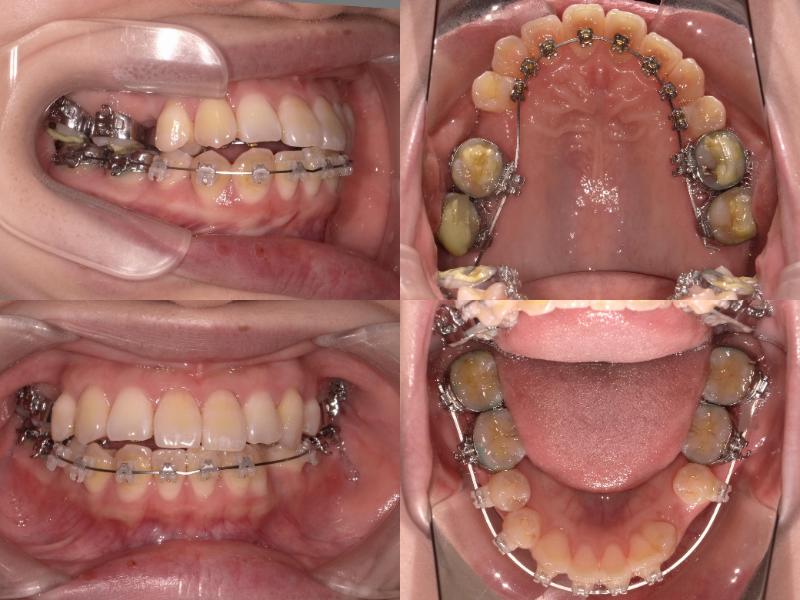

上下左右5番を抜歯し、上顎6番を口蓋正中縫合部からアンカースクリューで固定。

さらに、上顎2・3番の間に埋入したアンカースクリューから前歯を圧下し、口元の突出感とディープバイトの改善を図りました。

左上7番は再根管治療を行いできるだけ保存しましたが、矯正治療途中で症状が悪化したため抜歯となりました。

左上7番は再根管治療を行い経過観察としていましたが、治療途中で症状が悪化したため抜歯となりました。

上顎6番を口蓋正中縫合部からアンカースクリューで固定し、さらに上顎2・3間に埋入したアンカースクリューから前歯を圧下しました。